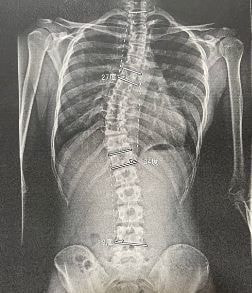

・こどもの健康相談各種…不登校、発達、夜尿症、側弯症